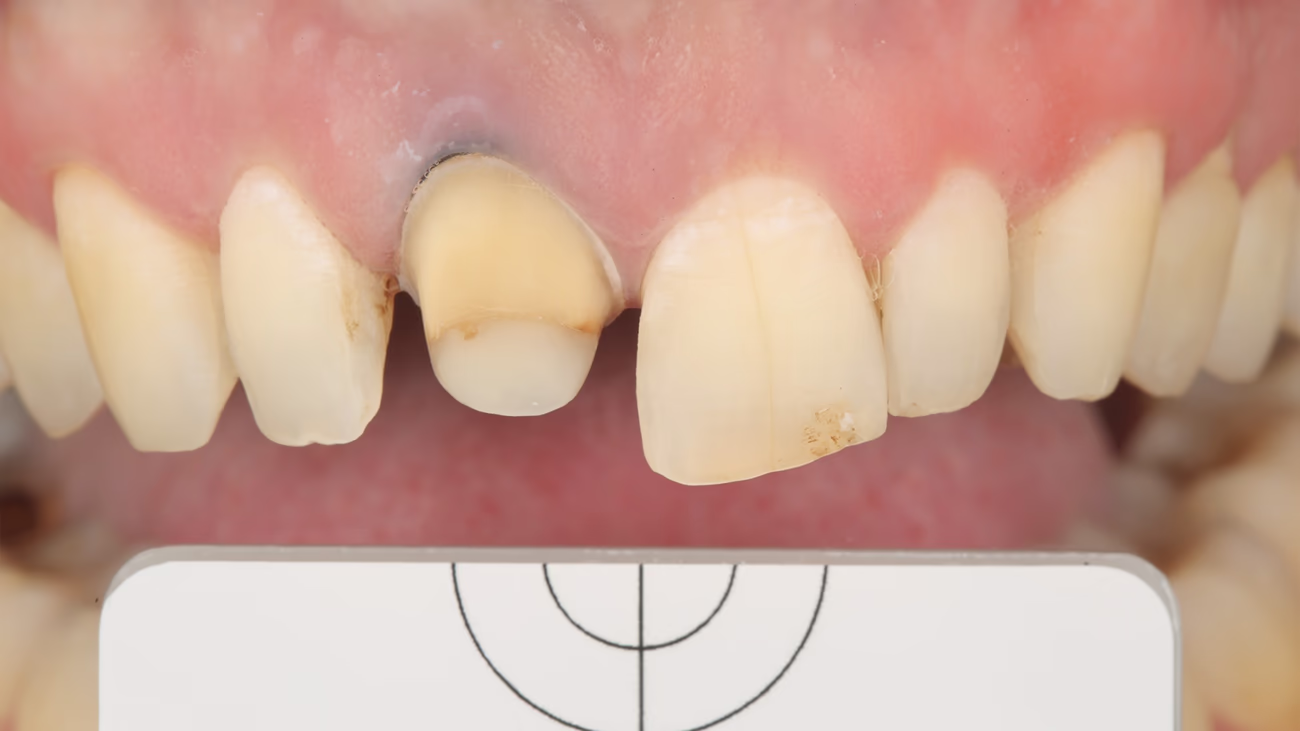

Фінішну лінію на зубі 11 потрібно залишити на тканинах зуба, тому висікався весь композит. Дизайн реставрації – 3/4 коронка. У такому разі упор, що утворюється при препаруванні з пала тинального боку, забезпечує правильне позиціо нування при фіксації реставрації.

Препарування зуба провадилося за допомогою операційного мікроскопа. Створювався не обхідний простір для керамічної реставрації на рівні м'яких тканин.

Після закінчення першої фази препарування алмазними борами Komet (крупнозернистими) була зроблена ретракція однією ниткою без просочення 000, яка забезпечує вертикальну ретракцію. Далі за допомогою полірувальних алмазних борів (з червоним маркуванням) ми змістили вестибулярну фінішну лінію апікальніше, до нового рівня зеніту. Це дозволяє сховати і зробити плавний перехід зуб – кераміка.

Перед фіксацією тимчасової реставрації на зуб 11 зробили фото обробленої кукси зуба з поляризаційним фільтром і сірою картою. Це додаткова інформація для зубного техніка про стан та колір кукси зуба.